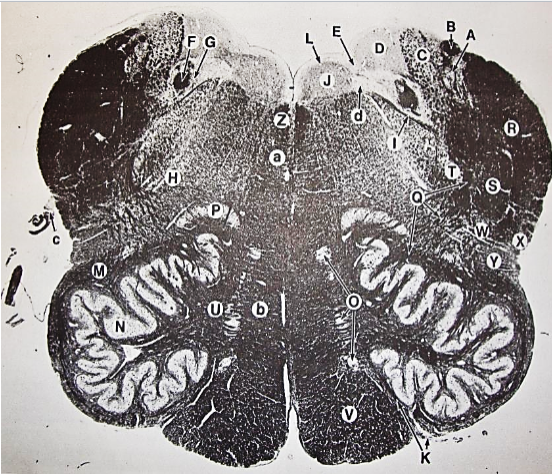

A

fasciculus gracilis

B

gracile nucleus

C

fasciculus cuneatus

D

cuneate nucleus

F

internal arcuate fibers

G

decussation of internal arcuate fibers

H

medial lemniscus

I

hypoglossal nucleus

J

dorsal motor nucleus vagus

K

solitary fasciculus

L

solitary nucleus

M

dorsal longitudinal fasciculus

N

spinal trigeminal tract

O

spinal trigeminal nucleus

P

posterior spinocerebellar tract

Q

anterior spinocerebellar tract

R

spinal lemniscus

S

lateral vestibulospinal tract

T

rubrospinal tract

U

lateral reticular nucleus

V

medial accessary olivary nucleus

W

pyramidal (corticospinal) tract

X

arcuate nucelus

Y

medial longitudinal fasciculus

Z

tectospinal tract

a

fascicles of hypoglossal nerve